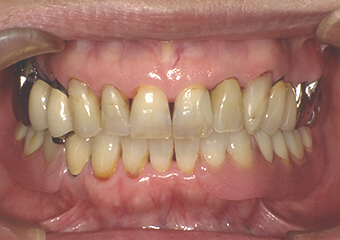

金属のバネのない入れ歯(下顎)

金属のバネを使用しない“ノンクラスプデンチャー”の製作も可能です。保険適用の義歯と比較して外観の回復の点で大きなメリットがあります。